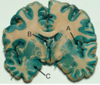

Label the arteries that supply A-C [3]

A

A = anterior cerebral artery (upper

and medial parts of the cortex)

(orange)

B = middle cerebral artery (lateral

areas of the frontal, parietal, and

temporal lobes) (white)

C = posterior cerebral artery (occipital

lobe and inferior parts of the

temporal lobe) (blue)